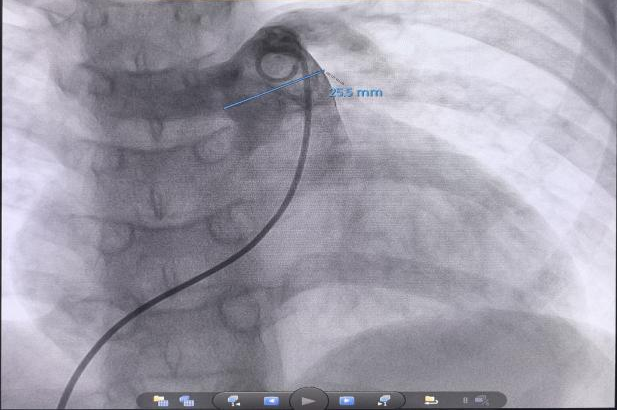

手术由心脏中心二病区肖云彬教授、杨舟教授主刀,在麻醉与监护保障下完成精准消融操作。术后即刻评估显示,小涵平均肺动脉压较术前下降26%,肺血管阻力下降17%。小涵术中及术后生命体征平稳,目前恢复良好,顺利出院。

本次手术体现了儿童PADN手术的显著技术挑战和重要突破。肖云彬表示,儿童肺动脉结构纤细,血管壁薄,且长期高压状态下常伴有血管形态改变,对术中的导管操作和消融定位提出了极高要求。儿童青少年处于生长发育关键期,手术需在追求即时血流动力学改善的同时,充分考虑长期生长发育影响。为此,该院在术前由医务部牵头,组织心脏中心、麻醉科、影像科、伦理委员会等多部门进行了系统严谨的技术论证和伦理审查,并特邀南京市第一医院张航教授参与指导,制定了完善的手术预案。